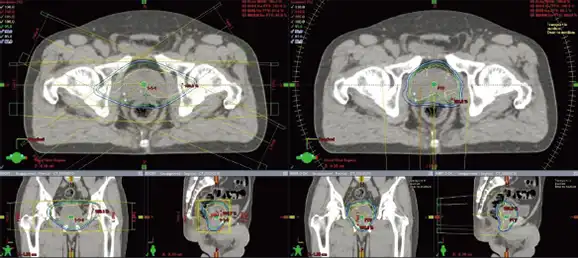

強度変調回転放射線治療(VMAT)とは

強度変調回転放射線治療(VMAT:Volumetric Modulated Arc Therapy)とは、リニアックが回転しながら連続的に放射線を照射することで、腫瘍の形状や位置に合わせて放射線の強度や照射範囲を細かく調整する治療法です。従来のIMRT(強度変調放射線治療)と比べて、照射時間が短縮されるとともに、より高精度な線量分布が得られるため、腫瘍への集中治療と正常組織への影響軽減が同時に実現できます。これにより、患者さんの負担が少なく、効率的な治療が可能となっています。

両側に広がる病変に対して、従来は十分な放射線治療ができませんでしたが、VMATを用いることで治療を行うことができるようになってきました。